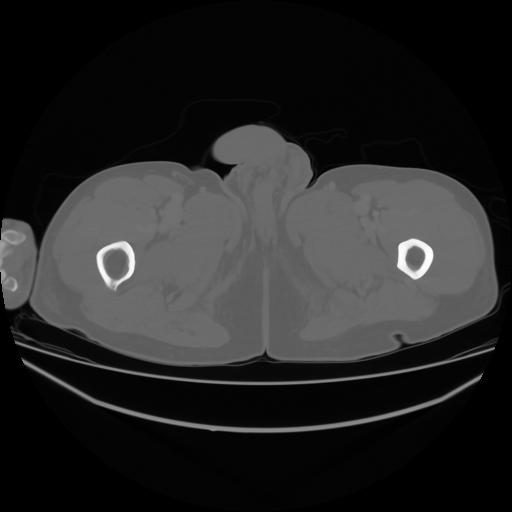

4 CUERPO,CE,Axial,3.0,CUERPO,,